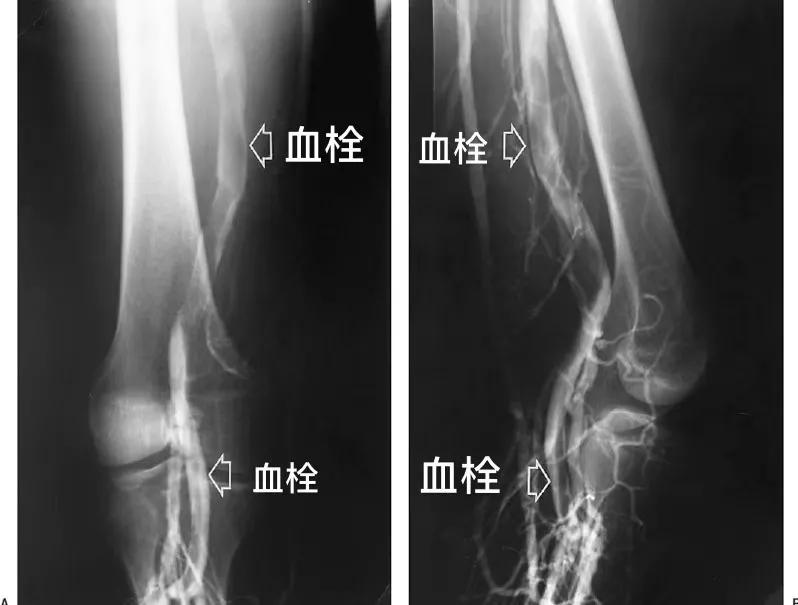

继疫情期间广受好评的下肢静脉曲张“空中门诊”之后,张强医生集团启动 静脉血栓“空中门诊” 视频咨询服务 ,针对困扰下肢静脉血栓患者的常见问题提供快速、专业、安全、有效的帮助。

✔腿上患深静脉血栓,如何预防发生肺栓塞?

✔髂静脉发生血栓,可以取出或者溶解吗?